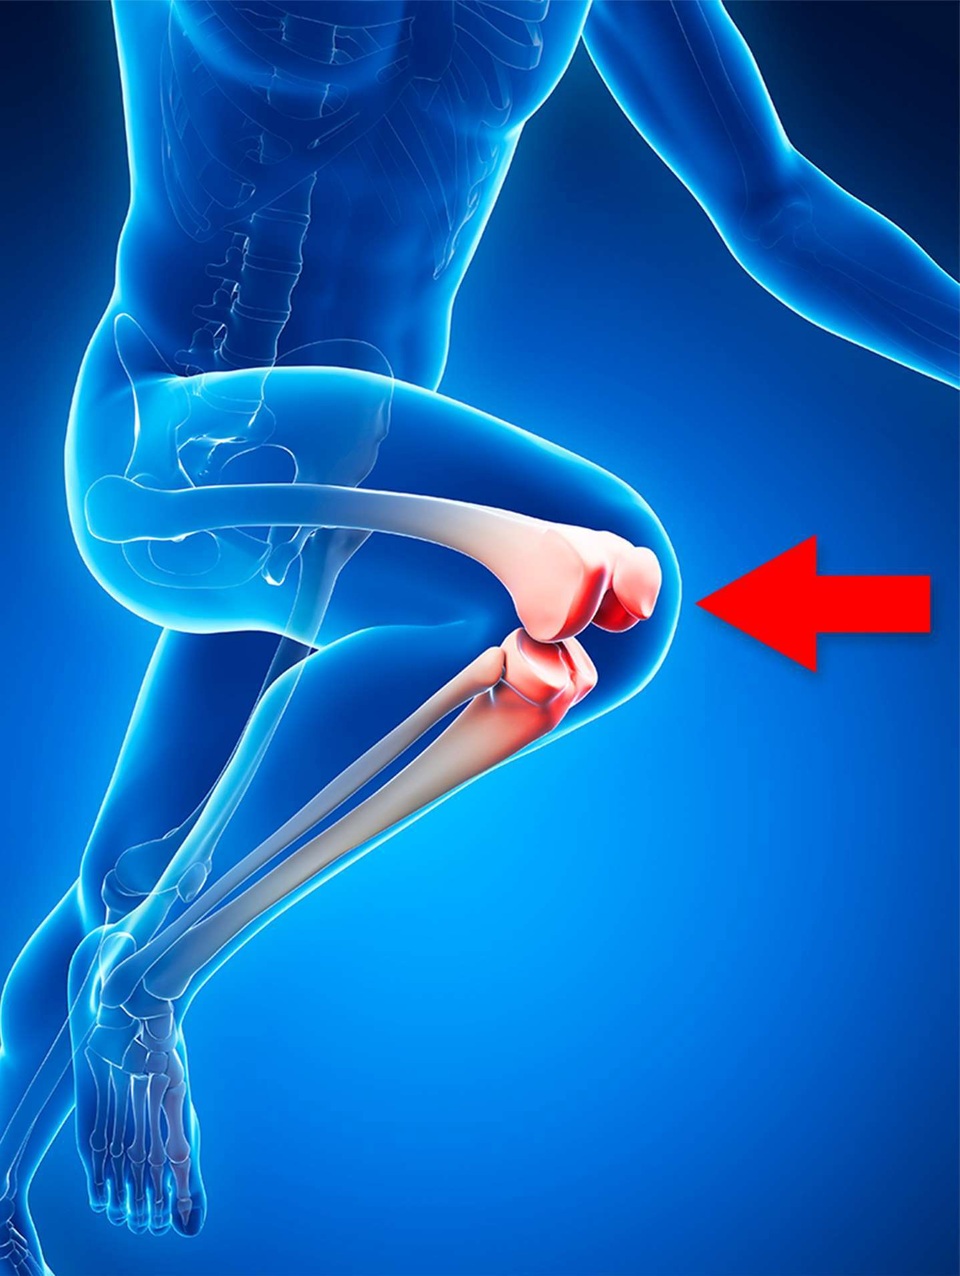

Bệnh khớp gối của người chạy bộ là nguyên nhân hay gặp nhất gây đau đầu gối ở người trẻ. Tình trạng này là do xương bánh chè cọ xát vào đầu xương đùi. Ngay cả những người không chạy bộ cũng có thể bị tình trạng này. Các triệu chứng cổ điển là đau dưới xương bánh chè khi lên xuống cầu thang. Vấn đề hay gặp những người năng vận động, tuổi từ 20-60.

Cách khắc phục: Cách khắc phục bao gồm tăng cường các cơ ở cẳng chân giúp xương bánh chè không cọ sát vào đầu xương đùi, cũng như rút ngắn sải chân khi đi hoặc chạy. Khi sải chân được rút ngắn, nó sẽ giảm tải cho xương bánh chè và giảm đau.